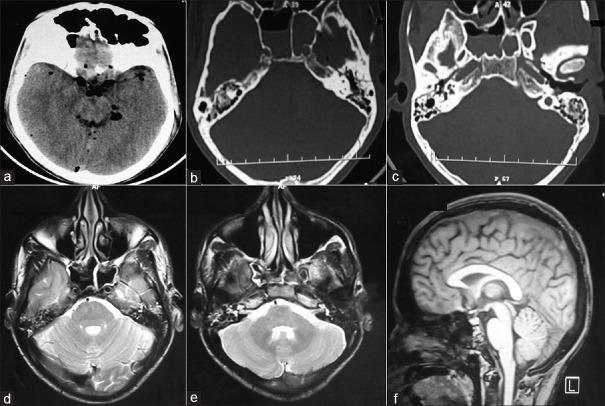

Bilateral abducens and facial palsy following head injury are extremely rare. We present a patient with post-traumatic bilateral facial and abducens palsy. There were bitemporal fractures that did not correspond with the facial canal. Despite complete facial palsy with axonal degeneration and > 90% facial muscle degenervation, conservative management helped. This report highlights the importance of conservative management in post-traumatic complete facial palsy especially when the fracture line does not correspond with the facial canal.